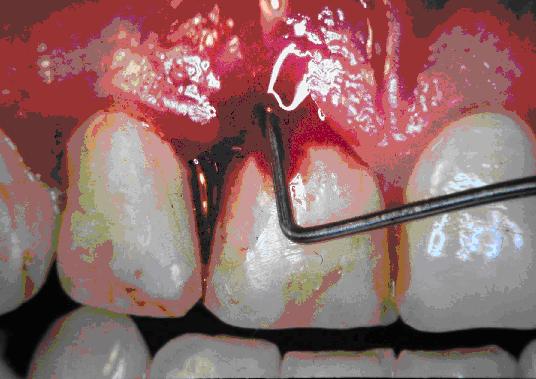

Slika 3. Sondiranje obzobnega žepa z graduirano sondo pri napredovali bolezni obzobnih tkiv.

Slika 4. Sonda na dlesni kaže osem milimetersko globino žepa.